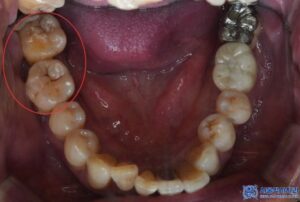

위 환자분은 50대 중반의 남성분으로,

오른쪽 위, 아래 어금니 잇몸이 많이 붓고

흔들림과 통증이 있다고 하셨습니다.

진단 결과, 상악 우측 작은 어금니와

하악 우측 큰 어금니 2개 부위에

만성복합염증이 광범위하게 퍼져 있었고,

염증으로 인해 뼈도 많이

손실된 상태였습니다.

이로 인해 세 치아 모두 흔들림이 심했고,

보존하기 어려운 상태였기에

발치 후 임플란트를 결정하였습니다.